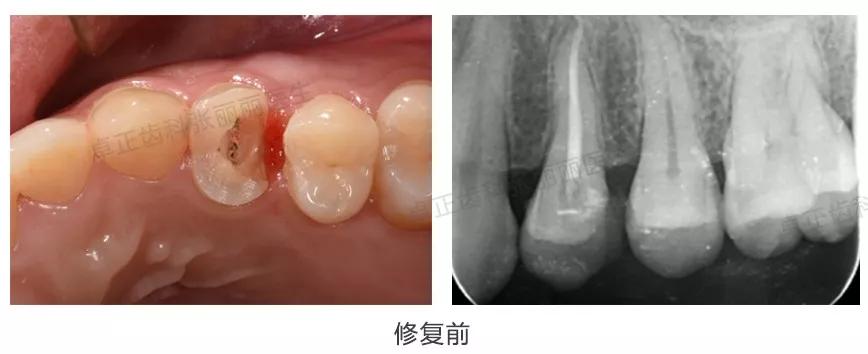

▍ 桩核冠

当后牙缺损面积大,剩余牙体组织不能为全冠提供固位力时,同样需要在根管内加桩来增加固位。